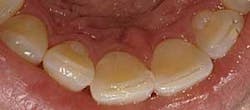

What should be photographed and reviewed with a patient? Items that should be documented in the digital patient record fall in this category. These include areas of visible pathology such as bruxism (Fig. 2), abfractions, attrition, caries, broken teeth, failed restorations, failed sealants, fracture lines, periodontal conditions including plaque, calculus (Fig. 3), root exposure, irregular or infected gum tissue, and soft-tissue lesions. It also is beneficial to take photos of normal teeth and tissue to show a patient the difference. A full-face portrait and full-smile photo also should be taken with a digital extraoral camera and imported into a patient’s file. These are helpful when discussing esthetic concerns, to have a baseline to compare to in the future, or for reconstruction in the unfortunate event that a patient loses part of his or her smile in an accident.

Next, tackle the bruxism and abfractions issue. Showing the patient photos of his or her worn teeth and abfractions usually communicates the message. If you observe that the patient still is confused, show another video presentation on bruxism and abfraction formation. At this point, the patient usually gets a grasp of the issue, and then it is much easier to discuss treatment options. When patients see, they understand. When they understand, they want treatment.